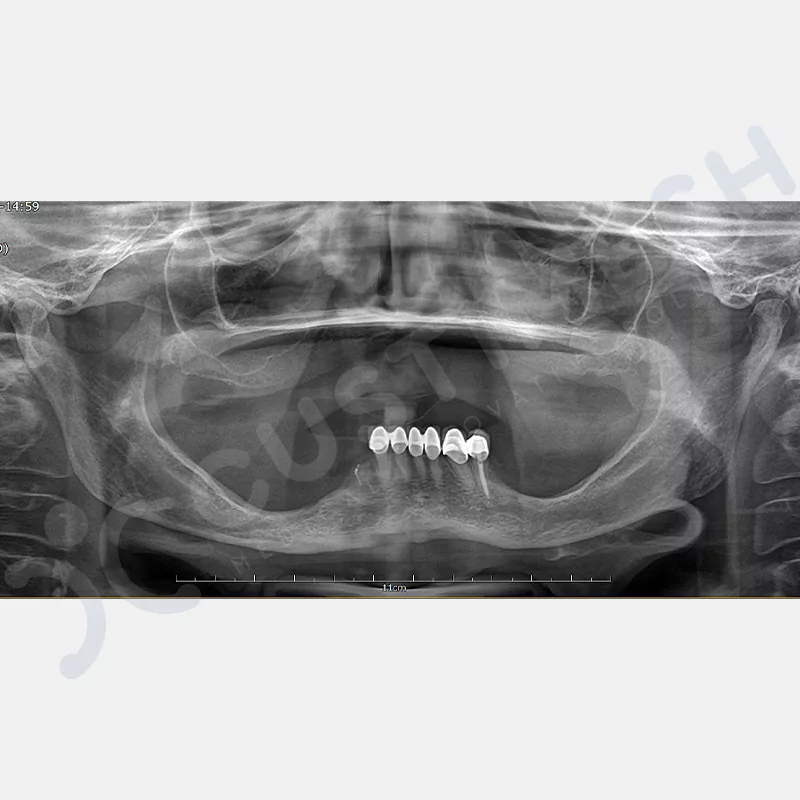

VAKA 1

VAKA 2

VAKA 3

VAKA 4